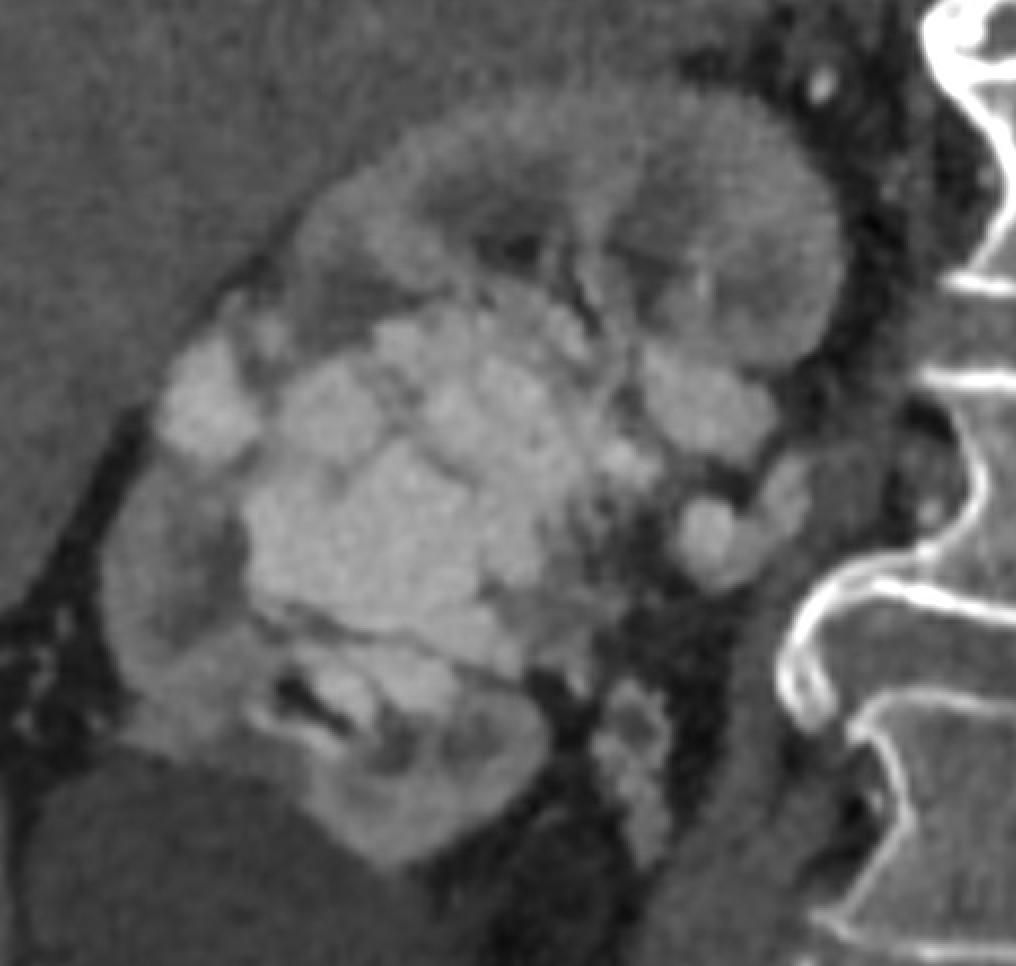

Dossier 1 : Volumineuse malformation artérioveineuse rénale, vraisemblablement secondaire à un carcinome à cellules claires du rein droit, de présentation atypique. Embolisation artérielle au 𝗦𝗾𝘂𝗶𝗱 (Balt) et au 𝗚𝗹𝘂𝗯𝗿𝗮𝗻 𝟮, à l’aide d’un micro-cathéter à ballonnet afin de ralentir le flux.